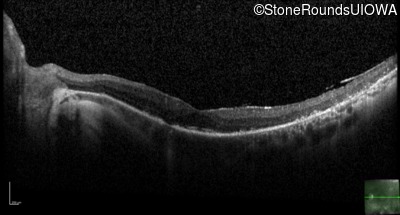

Optical Coherence Tomography - Right - 20/20

Exemplar / OCT Stack

OCT Stack